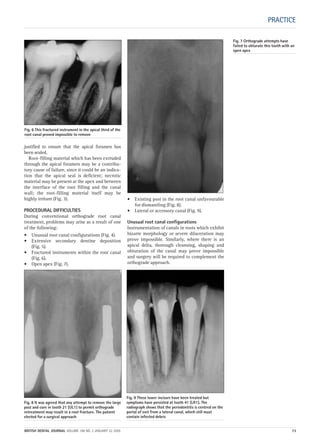

Fig. 6 A teenage patient who had a large periapical

lesion of a lower incisor is developing a cellulitis.

Fig. 7 External incision

may be required, and

the patient should

preferably be referred

to a general surgeon.

Fig 8 A patient who

complained of classic

‘cracked-cusp’ pain

was found to have such

a deep subgingival cusp

fracture that the tooth

was extracted.

06p299-305.qxd 24/08/2004 11:28 Page 303